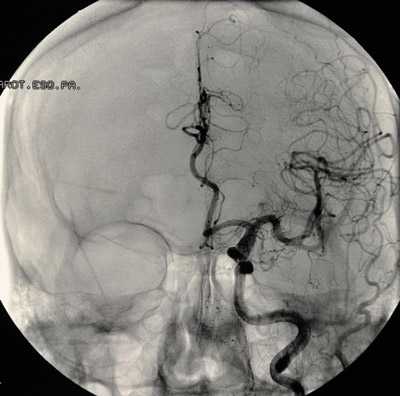

аневризма сосудов мозга на снимке

Перед планированием операции больной подвергается всевозможным обследованиям, включая анализы крови, мочи, коагулограмму, кардиограмму и т. д., как и при других оперативных вмешательствах. Для локализации и уточнения характера сосудистого образования проводят КТ, МРТ с контрастированием, ангиографию, ультразвуковое исследование с допплером.

- МРТ и/или КТ головного мозга, в том числе с использованием рентгеноконтрастного вещества, введенного в сосудистое русло пациента,

Обследование при аневризмах головного мозга включает проведение МРТ, эндоваскулярное исследование, ангиография с контрастом или КТ-ангиография, прием нейрохирурга и предоперационную подготовку (лабораторные анализы, ЭКГ, рентген легких).